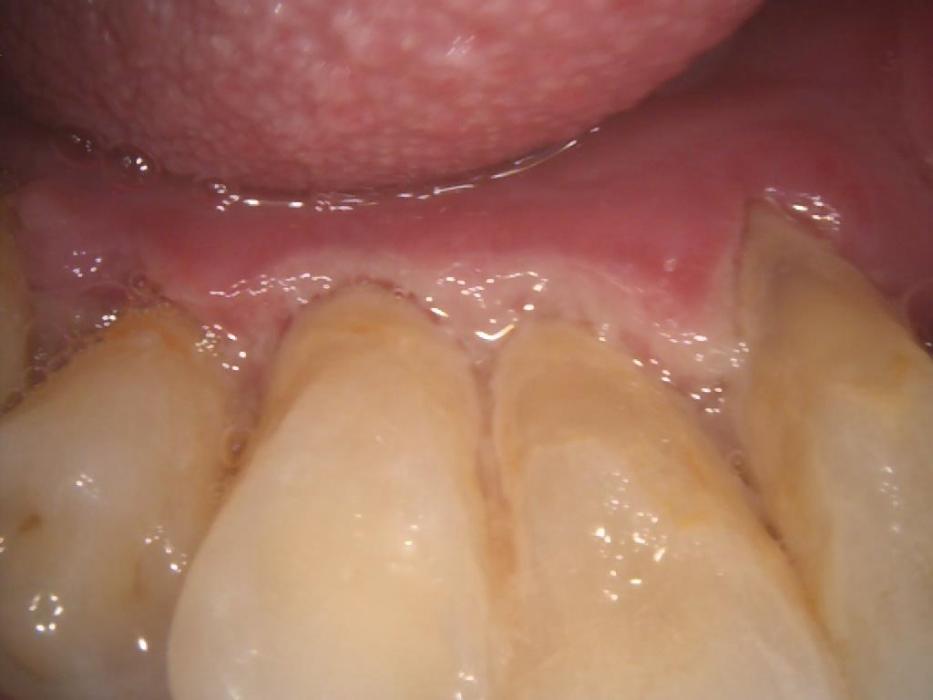

Diabetes affects your mouth by causing saliva production to be reduced. Saliva is a very important part of our oral health as it helps to prevent tooth decay by removing pieces of food and debris, preventing bacteria from spreading and even fighting the acids produced by the bacteria. The medications used to treat Type 1 and 2 Diabetes can cause the salivary glands to produce less saliva. When this occurs, the risk for cavities, gum disease, and other dental health issues increases. The high levels of glucose (sugar) found in your blood caused by diabetes and medications can cause the glucose to build up in your saliva. The glucose feeds the bad bacteria along with carbohydrates to form a soft, sticky film called plaque. When the plague is not removed properly, it can harden up near your gumline and turn into a tartar which is also known as calculus, which can cause gum disease.

Symptoms of oral health issues from Diabetes

- Red, swelling, bleeding gums

- Receding gums

- Gums pulling away from your teeth